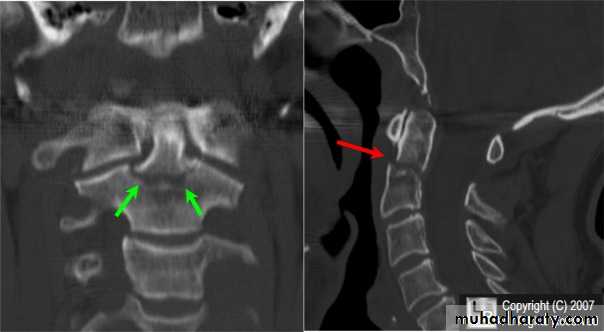

fracture of the atlas

fracture-dislocation of the atlanto-axial joint

force may fracture the neural arch, especially of the atlas

Or fracture the dens (odontoid process) of the axis.

DIAGNOSISX RAY

Anterio posterior X ray radiograph.lateral radiographs with the head in flexion and extension may revealinstability that is not shown in the routine lateral film.

oblique views

at 45° are especially helpfula special projection

through the open mouth.Computed tomography (CT)

and magnetic resonance imaging (MRI).